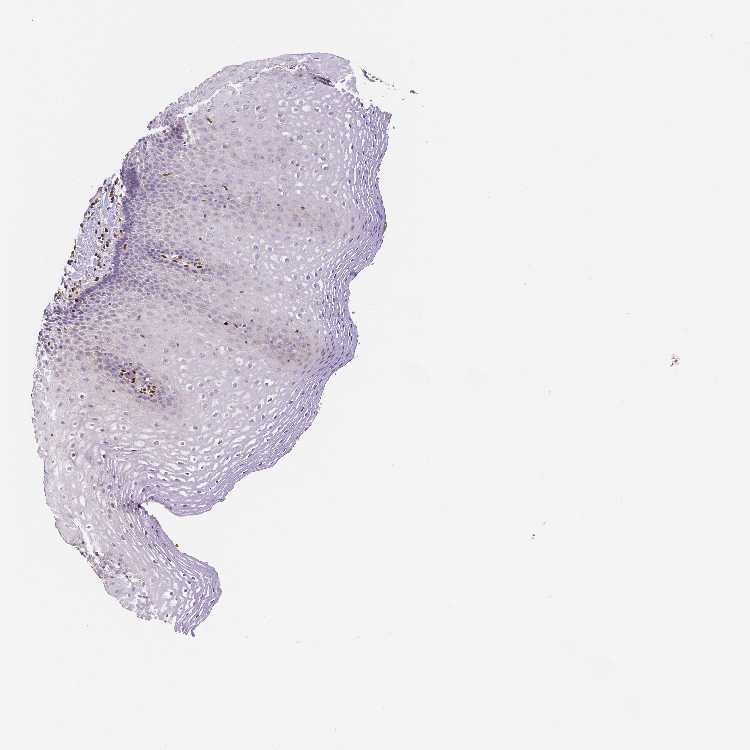

ESOPHAGUS - Antibody stainingi

Antibody staining in the annotated cell types in the current human tissue is reported as not detected, low, medium, or high, based on conventional immunohistochemistry profiling in selected tissues. This score is based on the combination of the staining intensity and fraction of stained cells.

Each image is clickable and will lead to virtual microscopy that enables deeper exploration of all samples and also displays staining intensity scores, fraction scores and subcellular localization as well as patient and tissue information for each sample.

Antibody HPA005533Antibody CAB068196Antibody CAB068197

Squamous epithelial cells Not detectedNot detectedNot detected